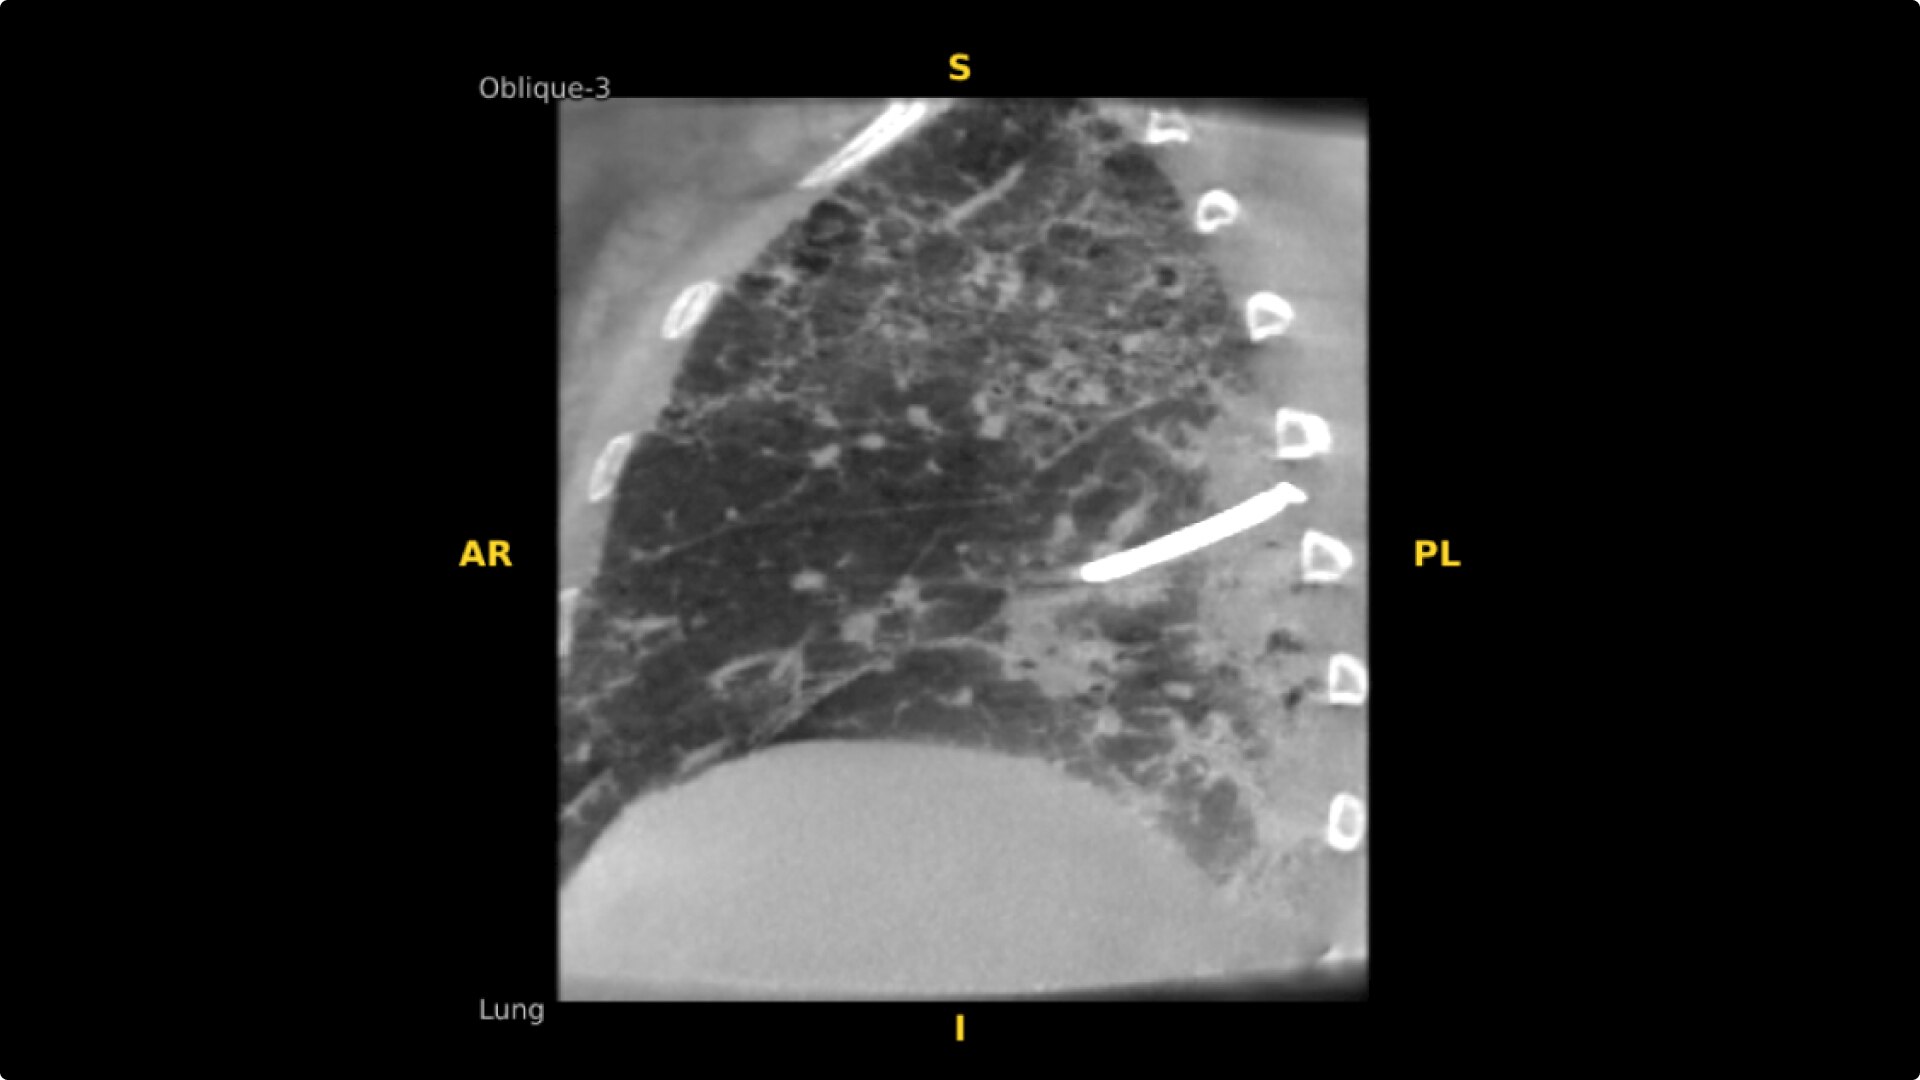

Select Lung Preset for optimized view of pulmonary structures. Easily change slices or adjust slice thickness for multiplanar assessment of lesions and bronchial structures.

Analyze CT-like images with the OEC 3D Volume Viewer which includes Multi Oblique Mode with reference coordinates, Window Level/Window Width, rotate, zoom, and more for quick and comprehensive tool-in-lesion confirmation.